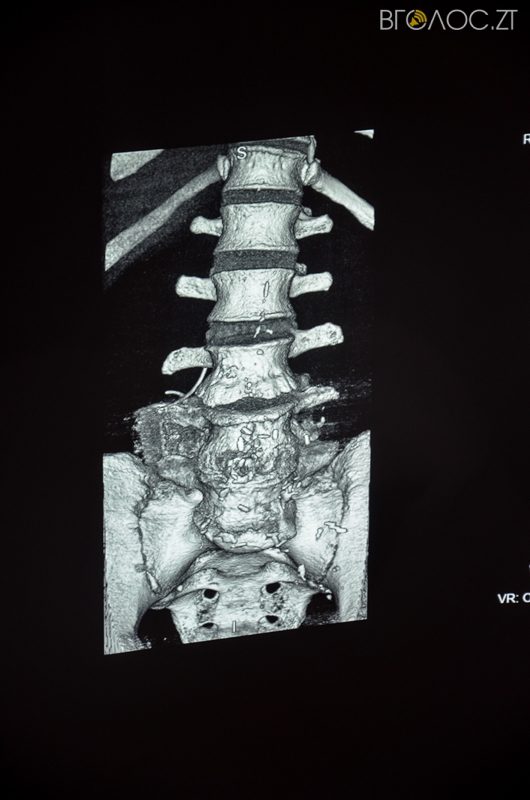

В обласній клінічній лікарні ім. О. Ф. Гербачевського відкрили роботу комунального комп’ютерного томографа 2016 року випуску, який обслуговуватиме пацієнтів щодня та цілодобово. Кошти на придбання обладнання виділили на сесії обласної ради у липні 2016 року. Комп’ютерний томограф є унікальним, оскільки робить сканування у 32 розрізах, водночас зменшує променеве навантаження на пацієнта.

«Такого комп’ютерного томографа ні у приватних, ні в комунальних установах немає. З його допомогою ми можемо забезпечити жителів нашої області високоякісною діагностикою та лікуванням», – розповів головний лікар обласної клінічної лікарні ім. О.Ф. Гербачевського Богдан Леськів.